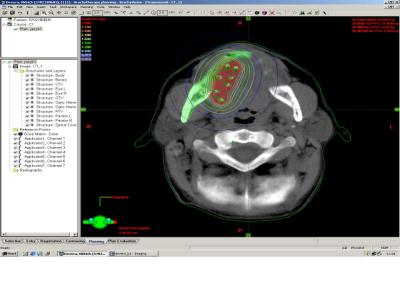

K plánování HDR brachyterapie se do nedávna využívaly snímky z C ramene, snímané v semiortogonální projekci (obr. č. 7 a 8), v posledních několika letech jsou využívány 3D snímky z CT (obr. č. 9).

Obrázek č. 9